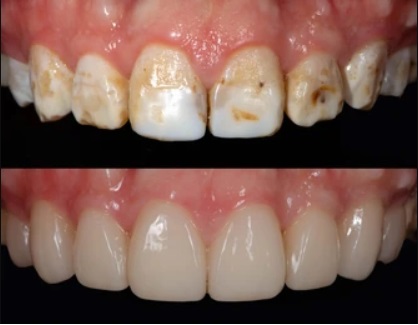

If you or a loved one is already experiencing dental fluorosis, there are treatment options available to improve the appearance of the teeth. The choice of treatment will depend on the severity of the condition and individual preferences. Some common treatment options include:

- Microabrasion:

This minimally invasive procedure involves removing a thin layer of enamel to reduce the appearance of stains and discolouration.

- Teeth whitening:

Professional teeth whitening treatments can help lighten the appearance of fluorosis stains and improve the overall aesthetics of the teeth.

- Dental bonding:

In cases where the fluorosis has caused more severe damage, dental bonding can be used to cover the affected areas and restore the natural appearance of the teeth.

- Veneers or crowns:

For severe cases of dental fluorosis, veneers or crowns may be recommended to cover the affected teeth completely and provide a long-lasting solution.